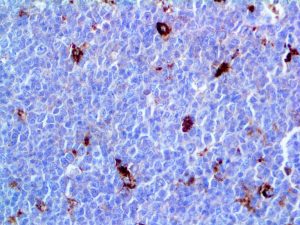

It is the ICU physician who is most likely to witness one of the deadliest manifestations of the abnormal immunological response, the cytokine storm syndrome (CSS). This response is also referred to by some as the cytokine release syndrome (CRS). CSS is characterized by continuous activation and expansion of macrophage and lymphocyte populations, which secrete large amounts of cytokines, causing the cytokine storm. This massive cytokine release is akin to hemophagocytic lymphohistiocytosis (HLH) disease, a syndrome characterized by initial unchecked and persistent activation of cytotoxic T lymphocytes and NK cells.

Clinical and laboratory manifestations of HLH include fever, enlarged liver and/or spleen, neurologic dysfunction, coagulopathy, liver dysfunction, cytopenias (i.e., low levels of erythrocytes, leukocytes, and/or platelets), hypertriglyceridemia, hyperferritinemia, hemophagocytosis, and eventually diminished NK cell activity as the immune system becomes progressively paralyzed. HLH can be familial (primary HLH) or secondary to another disease process (sHLH), such as rheumatic disease, in which it is referred to as macrophage activation syndrome (MAS, characterized by elevated ferritin).